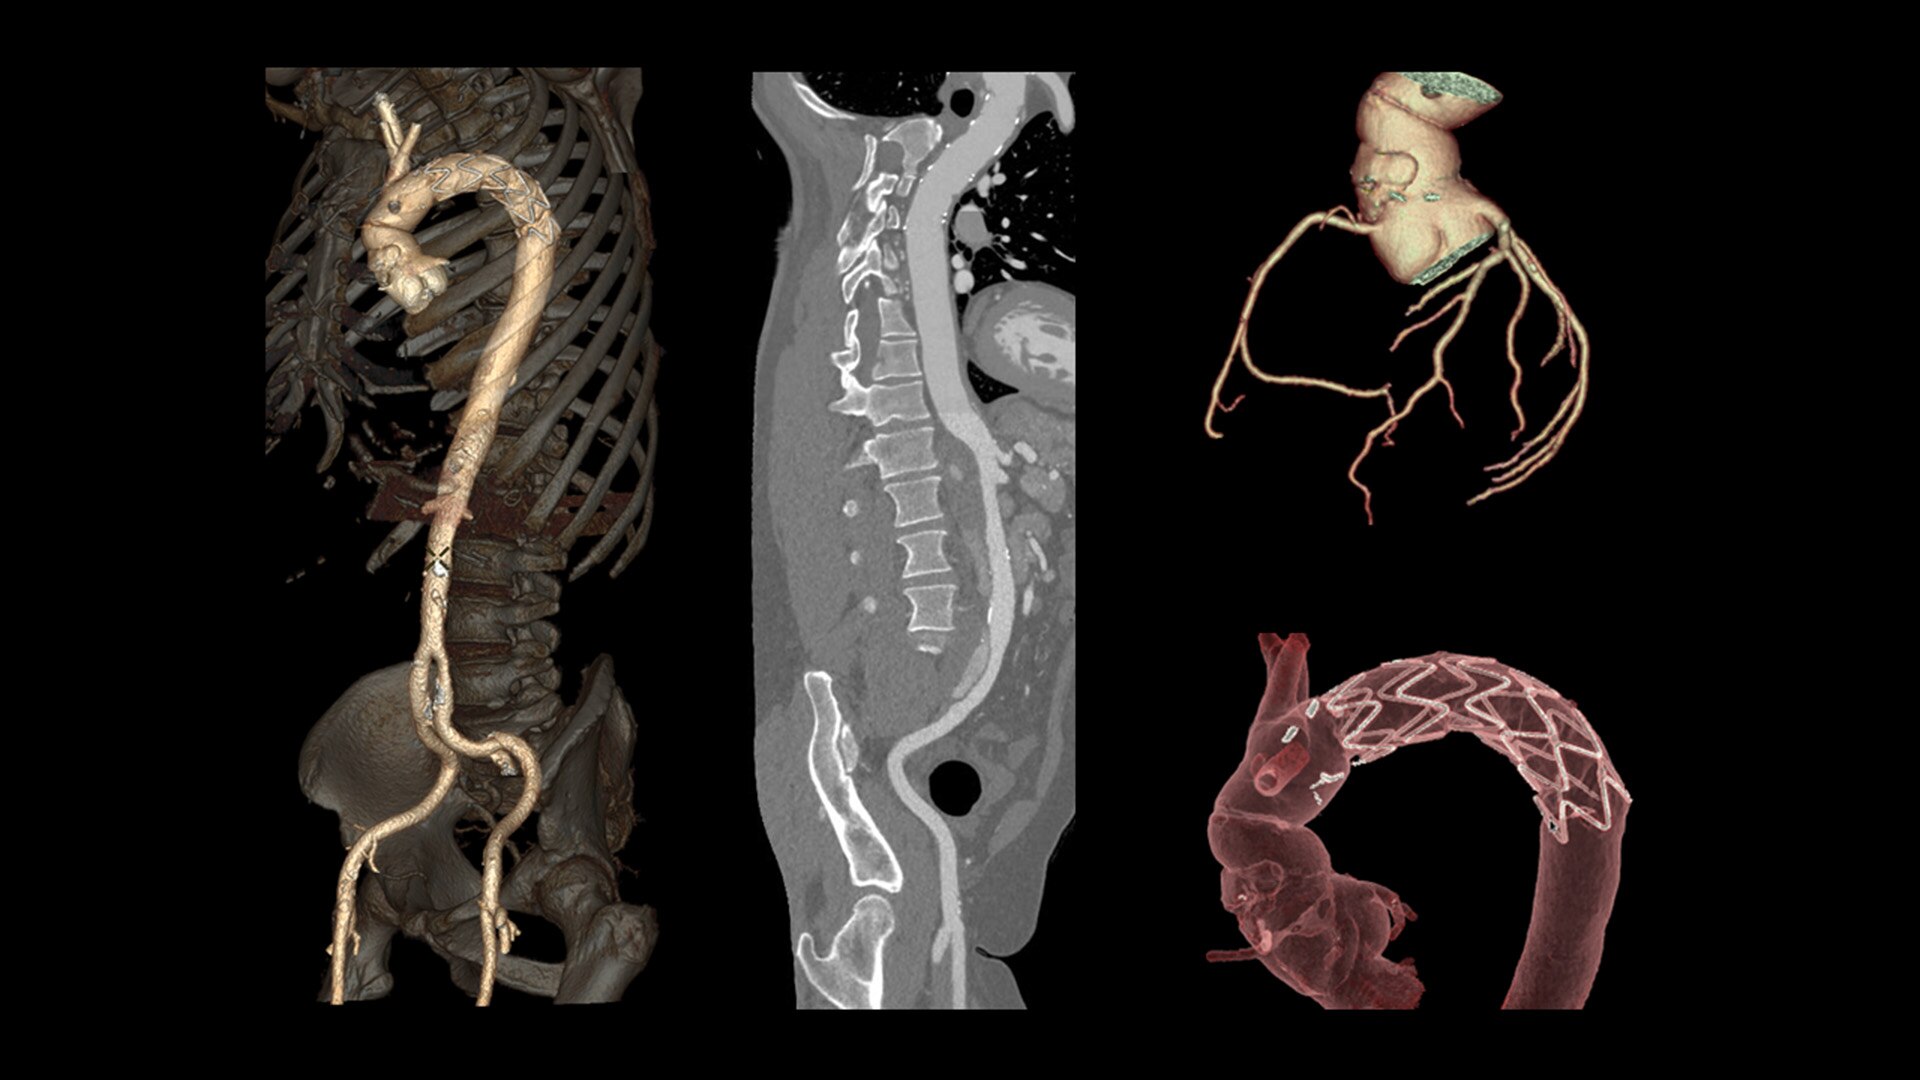

Cardiac CT has become a front-line, non-invasive imaging tool for diagnosing, treatment planning and monitoring of cardiovascular disease

Healthcare providers are striving to improve patient health but are struggling with increasingly complex exams, insufficient or inexperienced staff, and operational and capital efficiency. Revolution™ Vibe, designed to deliver leading-edge technology, features advanced cardiovascular capability. It improves patient access and operational efficiency, prioritizes patient care and supports your facility's growth with lower lifecycle costs.

Unlimited 1-Beat Cardiac is designed to provide consistent, high-quality imaging for accurate diagnoses, even in challenging patients with atrial fibrillation, breath-holding difficulties, heavily calcified coronaries, in-stent restenosis, and situations where an ECG trace is unavailable.